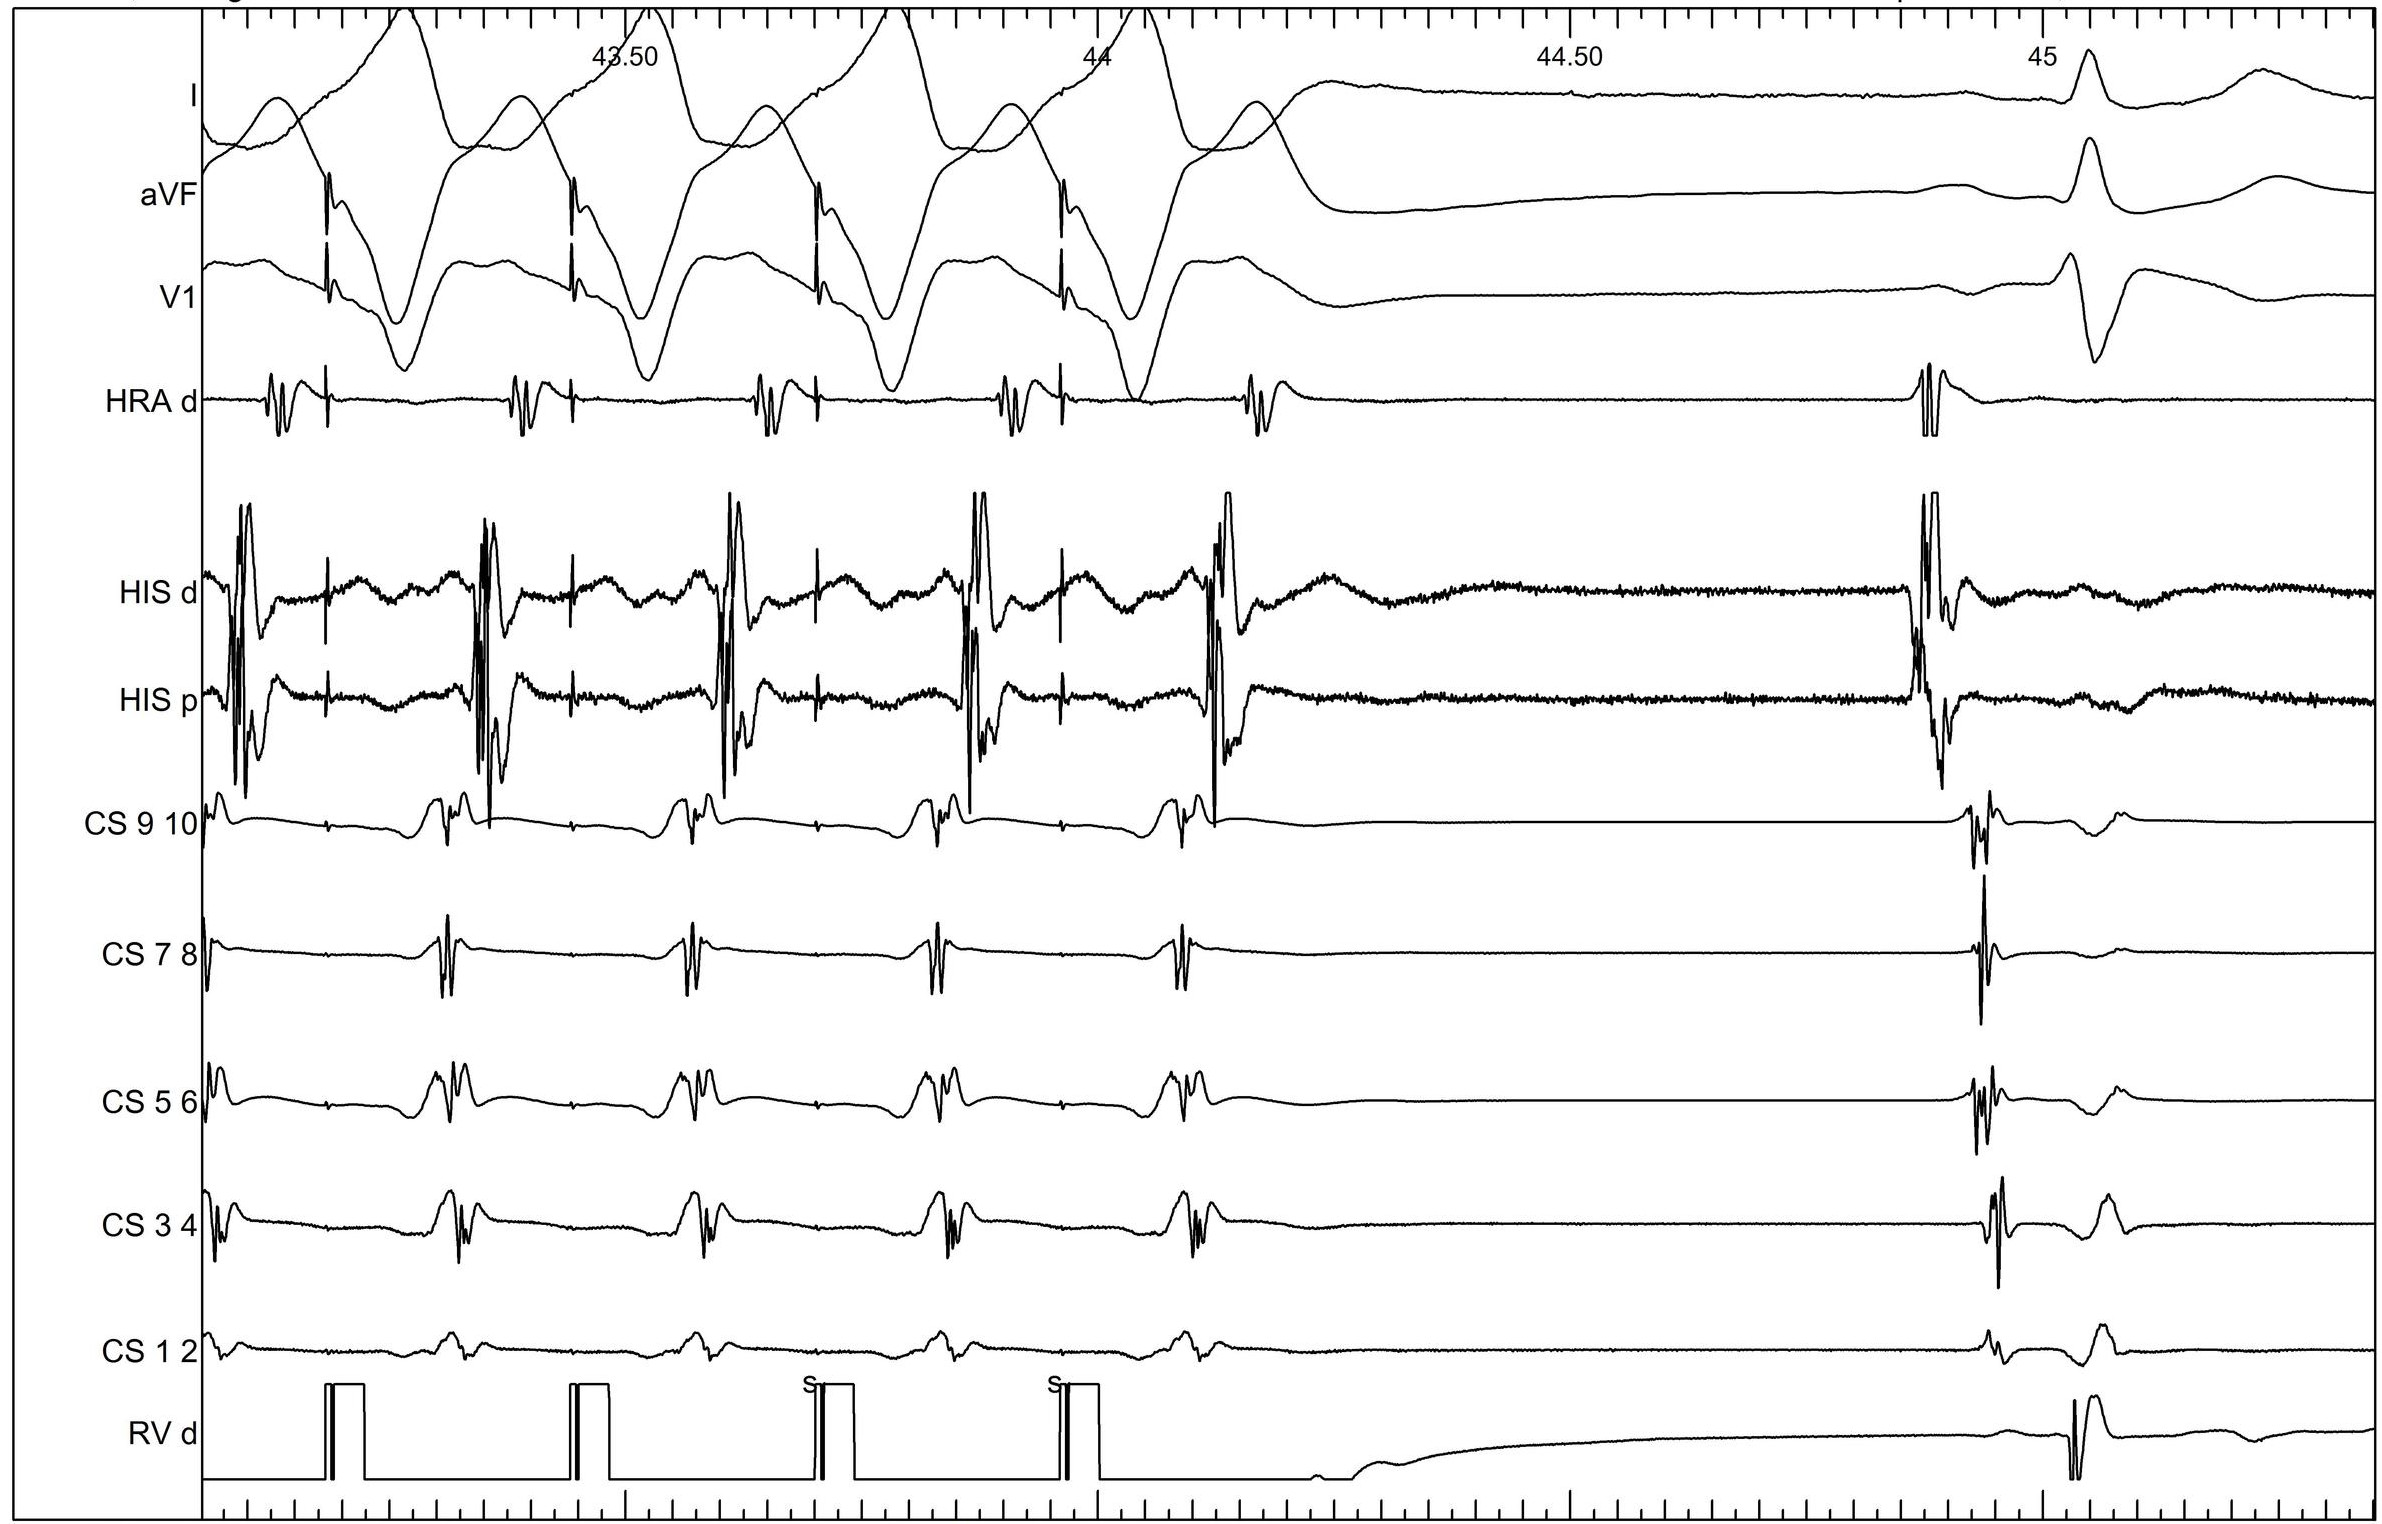

Ventricular burst pacing

05_vop_termination.jpg

Ventricular overdrive - Beginning

06_vop_onset.jpg